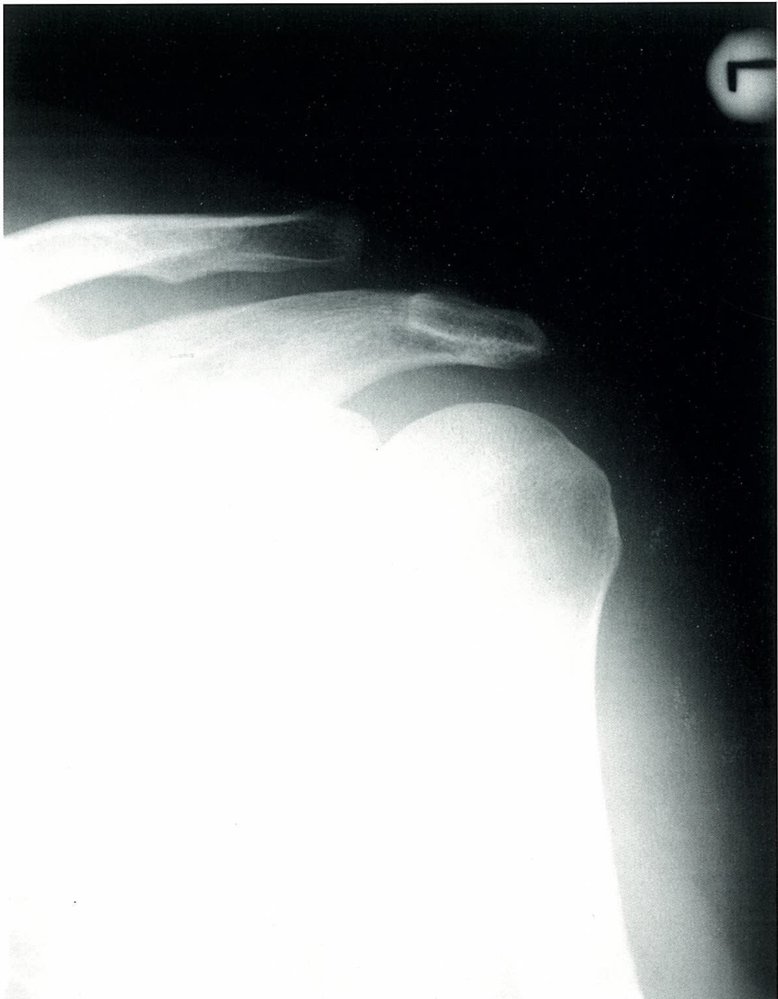

• X-ray (anterior-posterior view, oblique view, axillary view) of the shoulder joint, acromion, and scapula:

• Subluxation of the AC joint space

• Widening of the CC space

• Displacement of the clavicle

• Accompanying injuries (e.g., clavicle fracture)

• Visible deformity of the lateral aspect of the clavicle may be seen in types III and above